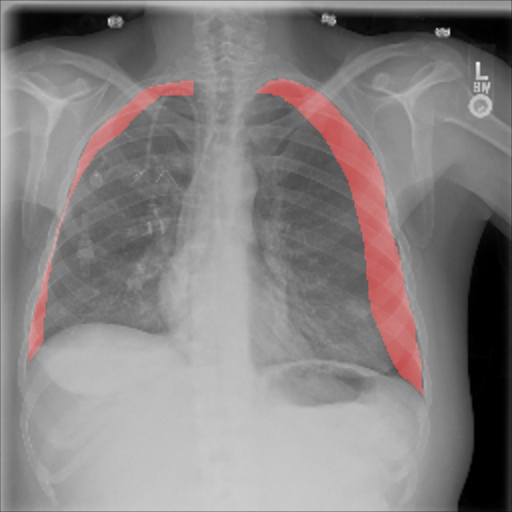

The pre-trained ResNet-50 was also employed as the patch-level classifier within the MIL approach. We chose the binary cross-entropy between the maximum patch score and the image-level label as the loss function. The batch size was selected as the number of patches per image. We trained with an initial LR of for 30 epochs and achieved an average AUC of 0.930.01 using this method. High patch scores (indicated by thicker red frames, cf. Fig. 5(c)) give a hint on the location of the pneumothorax.

As pixel-level ground truth annotations were available only for a subset of the images, 871 images in total were used for training the FCN for 400 epochs. As a loss function, a weighted cross entropy (25.0 for pneumothorax pixels and 0.5 for non-pneumothorax pixels in order to account for the smaller size of pneumothorax regions) was employed at pixel-level with an initial LR of . With an average AUC of 0.920.02, the overall performance of this method is worse than the CNN and MIL. On the other hand, the FCN generates pixel-level probabilities (cf. Fig. 5(d)), which indicate the location of the pneumothorax. The average Dice coefficient for positively classified cases is .

On the other hand, the FCN approach requires pixel-level annotations. These are usually difficult to obtain, but the network provides a localization of the pneumothorax, which forms an additional level of confidence and interpretability.

We achieved the best performance in terms of AUC using CNN, whereas the MIL and FCN provided higher confidence in terms of localization. This could guide radiologists by visualizing the image region responsible for the network’s decision, while simultaneously increasing the trust in the proposed deep learning architecture. Combining the proposed three methods as an ensemble, increased the overall classification performance, while MIL and FNC allow for a localization of the pathology. Future work could elaborate on other techniques to combine the three approaches, e.g. by cascading networks or merging the architectures into one multi-task network.